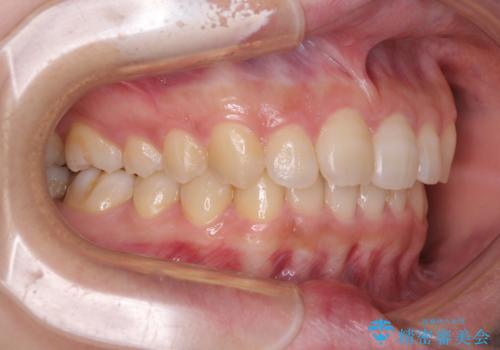

- 前歯のデコボコと奥歯の不正咬合を気にして来院された患者様です。

左右の大臼歯が全て鋏状咬合(シザーズバイト)になっており、治療が難航することが予想されましたが、インビザラインにより治療を行うこととしました。

最難関と思われたシザーズバイトは比較的短期間で解消されました。

しかし、治療中に2度の出産を経験され、治療期間は長くなってしまいましたが、咬みやすく、清掃しやすい歯列を獲得することができました。